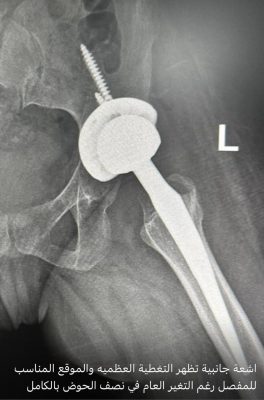

مضيفاً : وصلت المريضة للمستشفى وتم إجراء كافة التحاليل والفحوصات والإشاعات المطلوبة و التي أكدت إمكانية إجراء عملية تغيير مفصل كامل للورك بأمان رغم صعوبة التغيرات العظمية للورك وضمور العضلات وقصر الرجل وتمت العملية بنجاح ولله الحمد لتضاف للجراحات النوعية في جراحة استبدال مفصل الورك التي تتم في المستشفى ،وتؤكد على تطور الخبرات الطبية بالمستشفى بأحدث التقنيات الطبية الحديثة المتطورة عالمياً.

واختتم العتيبي حديثه مشيراً إلى أن المريضة بدأت في مرحلة التأهيل لاستعادة الحركة بدون ألم بمفصل ورك صناعي كامل.